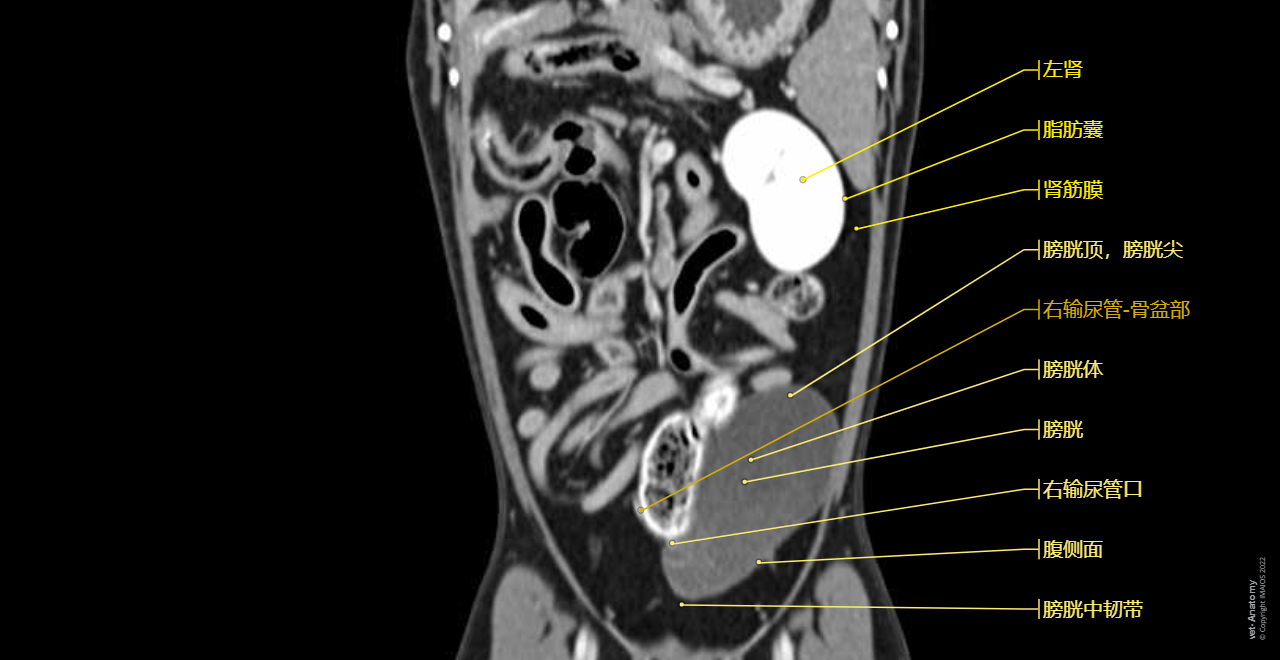

vet-Anatomy兽医图集的本模块是关于CT扫描的犬类腹部和骨盆。

CT图像来自一只健康的6岁阉割雄性犬。

在vet-Anatomy动物图集的此模块中,计算机断层扫描(CT)显示了标有解剖结构的犬科腹腔和骨盆横截面,并用3D图像显示犬科腹部。

CT图像存在3个平面方向(横向,矢状和背侧),并且使用两种对照方式(软组织/血管和骨骼)展现。本模块的末尾提供其他3D解剖图像,便于进一步了解犬科总体解剖结构,展示了骨骼、内脏(肝脏、脾脏、胰腺、消化道)、泌尿生殖系统、动脉、全身静脉系统(主要是尾腔静脉及其分支)、门静脉系统、肌肉和表面解剖的三维容积透视图。

毕业于欧洲兽医诊断影像学学会的Susanne AEB Boroffka博士(荷兰乌得勒支)对健康的6岁雄性阉割犬(拉布拉多猎犬)注射碘化造影剂并完成计算机断层扫描。

放射科医生(法国蒙彼利埃)Antoine Micheau博士和放射科医生(法国蒙彼利埃)Denis Hoa博士完成了图像显示、解剖标记和解剖释义工作。

Dog - Urinary organs: Kidney, Ureter, Urinary bladder, Male urethra